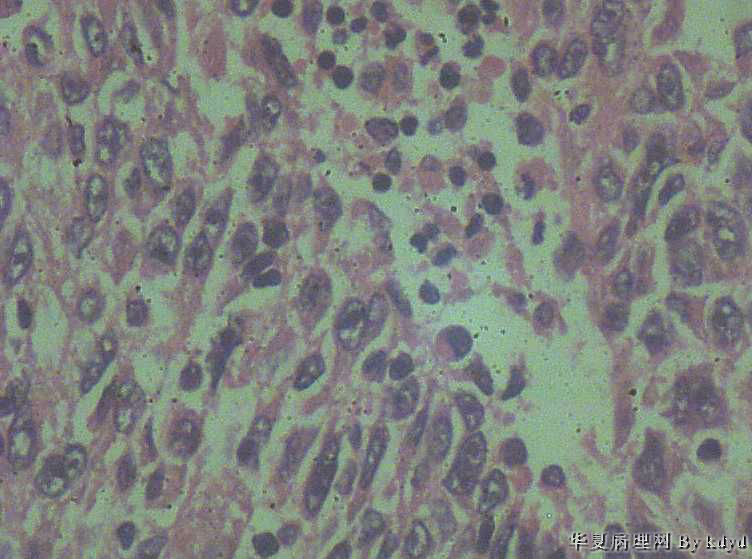

B3997左乳肿瘤--浸润性导管癌?

37岁,女。左侧乳腺肿块发现5个多月,伴隐痛。

手术见:肿块与周围组织分界不清,无明显包膜。

大体:不整形组织大小约3.5*35*2CM,未见明显包膜。质较软,切面浅黄色,一侧见一小囊腔直径约0.8CM囊壁较粗糙。

标签:乳腺浸润性导管癌 原位癌

浸润性乳腺导管癌?

IDC

乳腺浸润性导管癌

囊壁内大量炎细胞浸润,囊壁被覆细胞有明显异型,可见核分裂,考虑癌,不知有无陷阱

浸润性导管癌

应该是个浸润性导管癌

但是,片子质量欠佳

不太敢直接下

诊断乳腺浸润性导管癌确实有些担心,制片质量确实要提高,制作优良的切片,是正确诊断的前提。